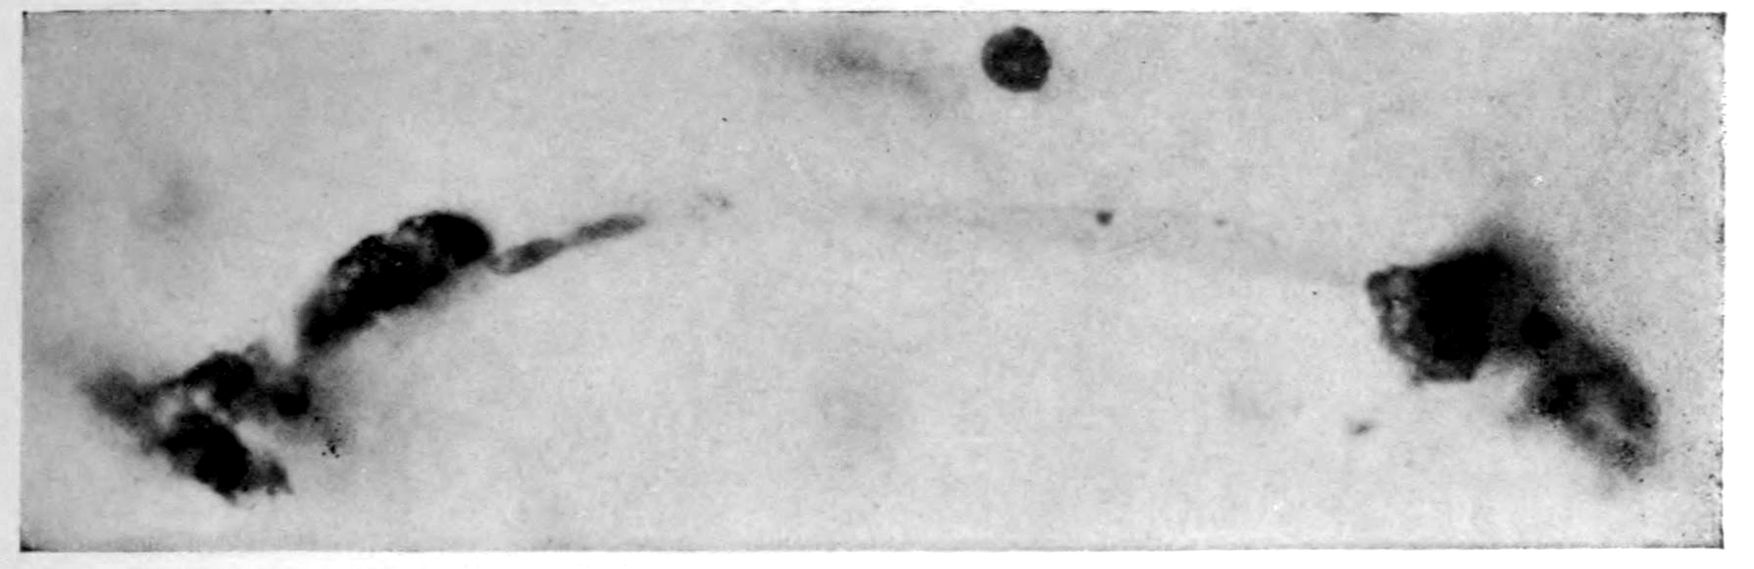

Case I. Spinal Cord (Three Levels) Showing:

A. Marginal sclerosis—effect of old meningitis now extinct.

B. Posterior column sclerosis—effect of meningitis about posterior roots also now extinct.

C. Bilateral pyramidal tract sclerosis—effect of cerebral thrombotic lesions.

Note distortion of tissues in B and C, partly artificial (tissues in places diffluent).

Vascular neurosyphilis—effects of syphilitic thrombosis of Sylvian artery 10 years before death. (Case 4.)

Case 4. (See previous figure for brain lesion.) Three levels of the spinal cord showing unilateral pyramidal tract sclerosis, 10 years after cerebral thrombosis.